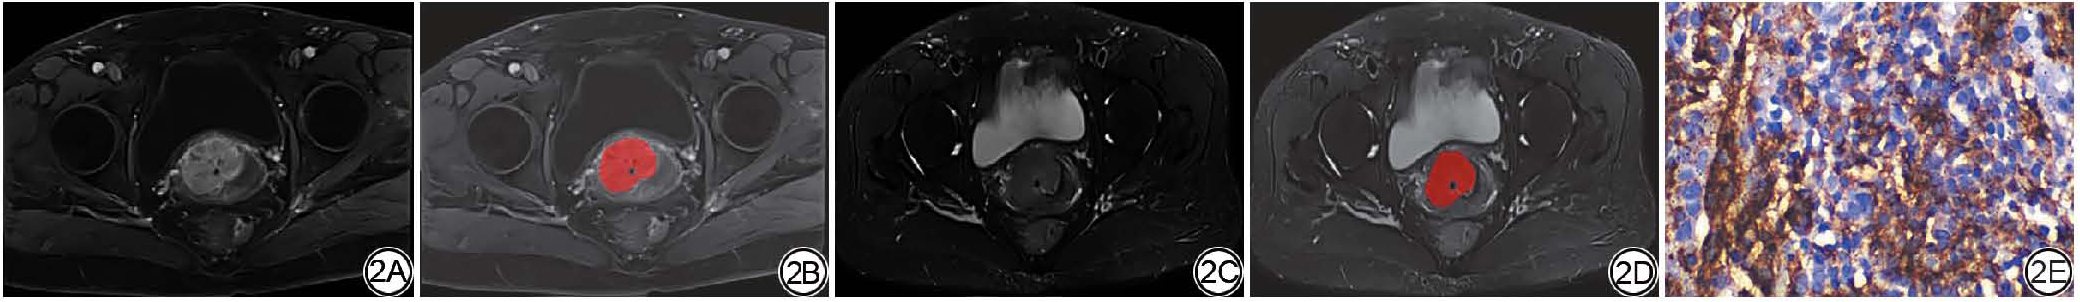

图1  女,58岁,宫颈鳞癌,PD-L1低表达。1A~1B:对比增强T1WI横截面图像(1A)及ROI勾画示意图(1B);1C~1D:脂肪抑制T2WI横截面图像(1C)及ROI勾画示意图(1D);1E:免疫组化染色图像(× 40)。PD-L1:程序性死亡受体配体1;ROI:感兴趣区。

Fig. 1  Female, 58 years old, cervical squamous cell carcinoma, low expression of PD-L1. 1A-1B: Cross section of contrast enhancement-T1WI image (1A) and schematic diagram of ROI sketch (1B);1C-1D: Cross section of fat suppression-T2WI image (1C) and schematic diagram of ROI sketch (1D); 1E: Immunohistochemical staining image (× 40). PD-L1: programmed death-ligand 1; ROI: region of interest.